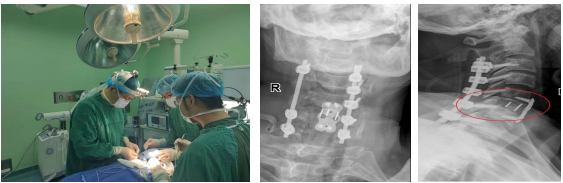

精准完成复杂手术。在充分术前准备基础上,3月19日省医-阿医骨科专家联合、由省医院脊柱外科张伟教授主刀,在患者全身麻醉状态下,为其精准施行“经前路颈5/6脱位切开复位钉板系统内固定术、椎间盘切除、椎管减压、Cage植入椎体间融合术+经后路颈3-7钉棒系统内固定术(8钉2棒)、椎管扩大减压、横突间植骨融合术”。手术顺利,术后右下肢肌力恢复至3级,右上肢肌力恢复至2+级。